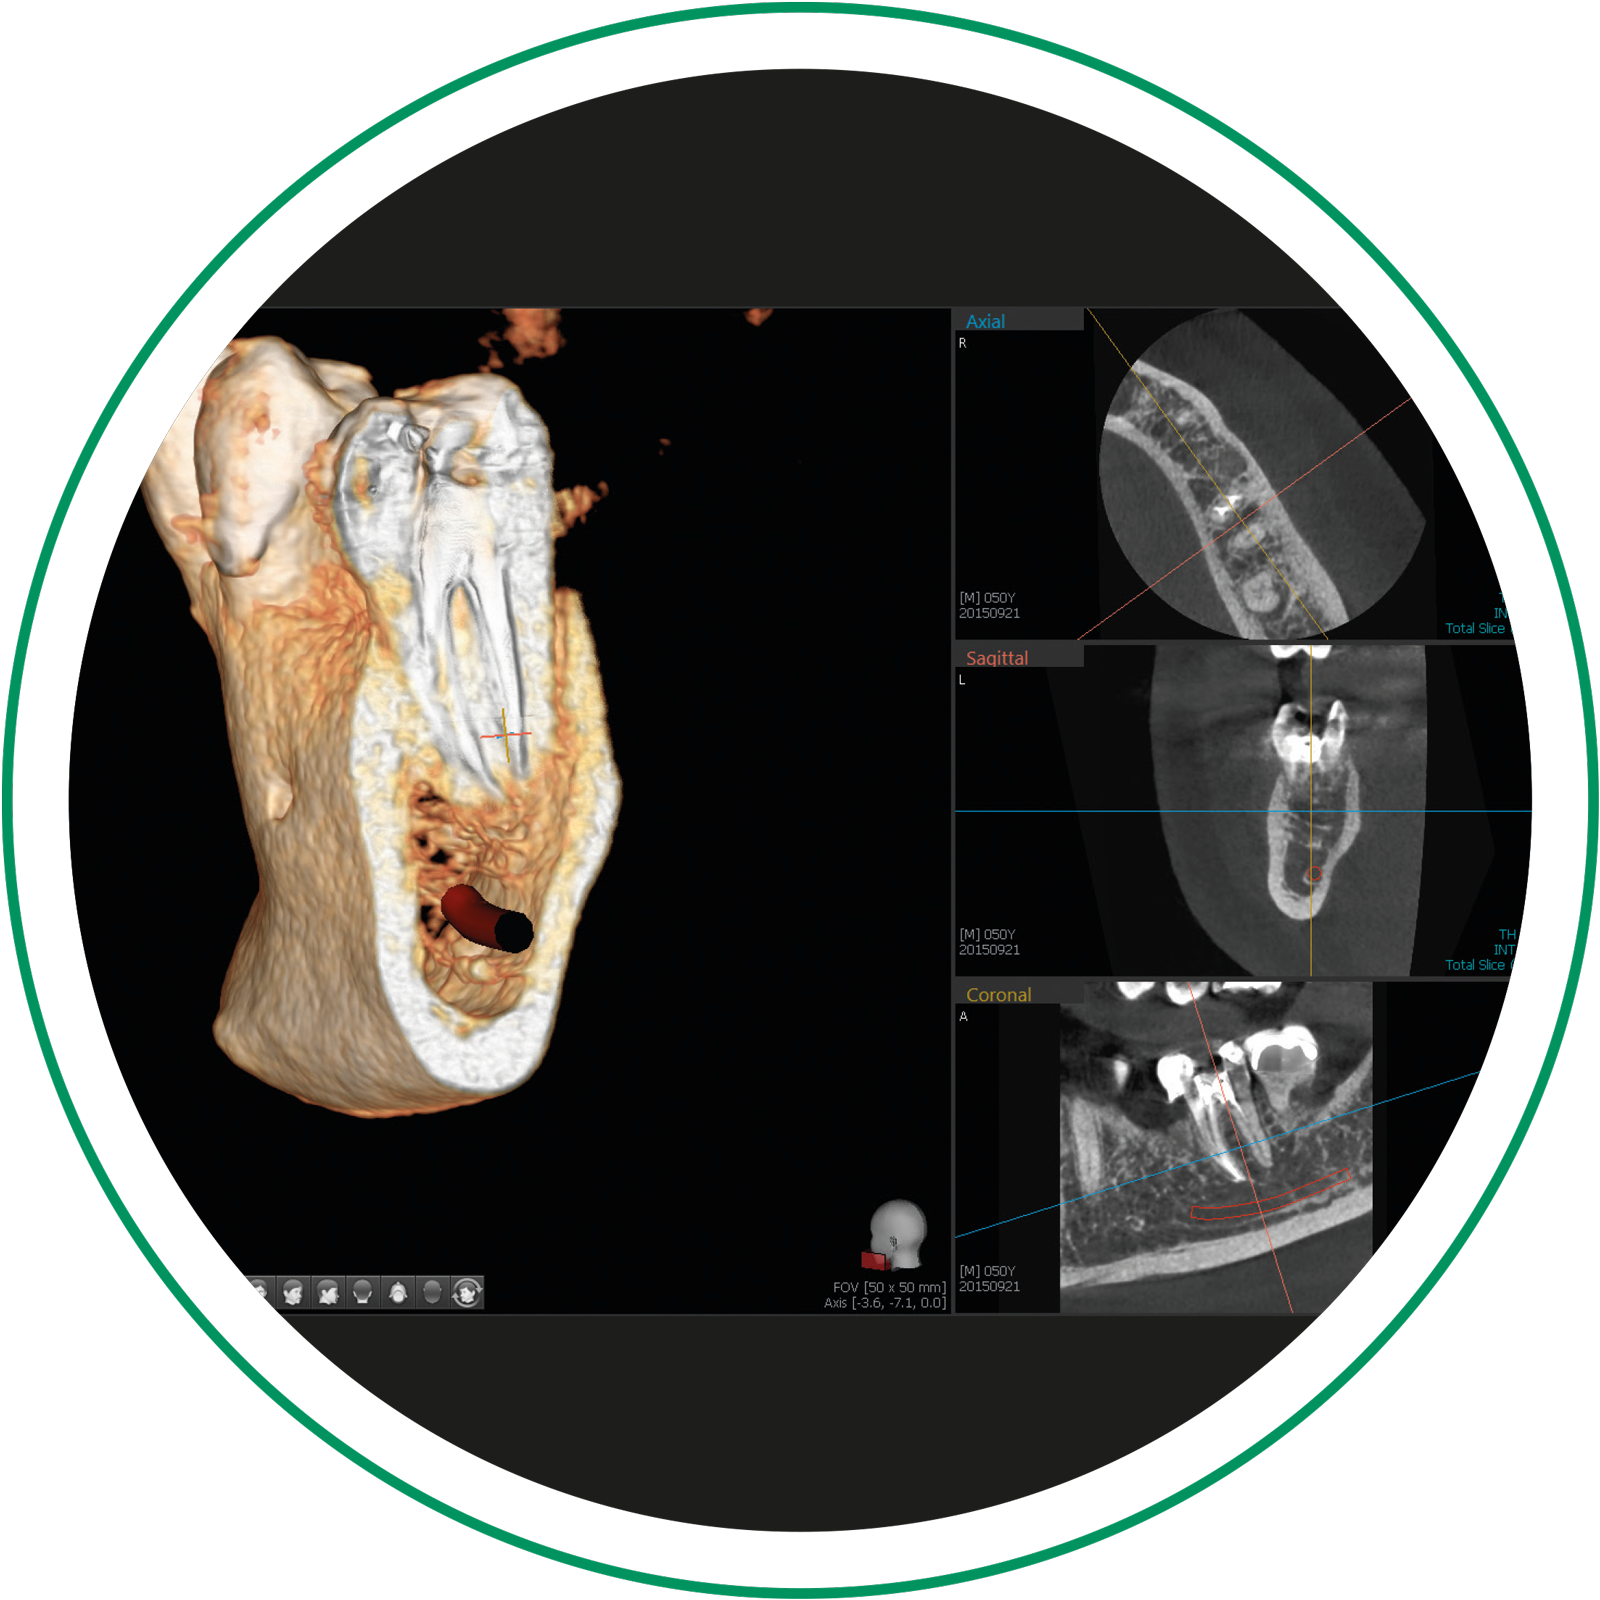

Il sistema diagnostico integrato per le diagnosi tridimensionali

Grazie ad un morso ed un poggiamento dedicato consente di effettuare diagnosi tridimensionali del terzo medio del massiccio cranico e di visualizzare i seni mascellari.